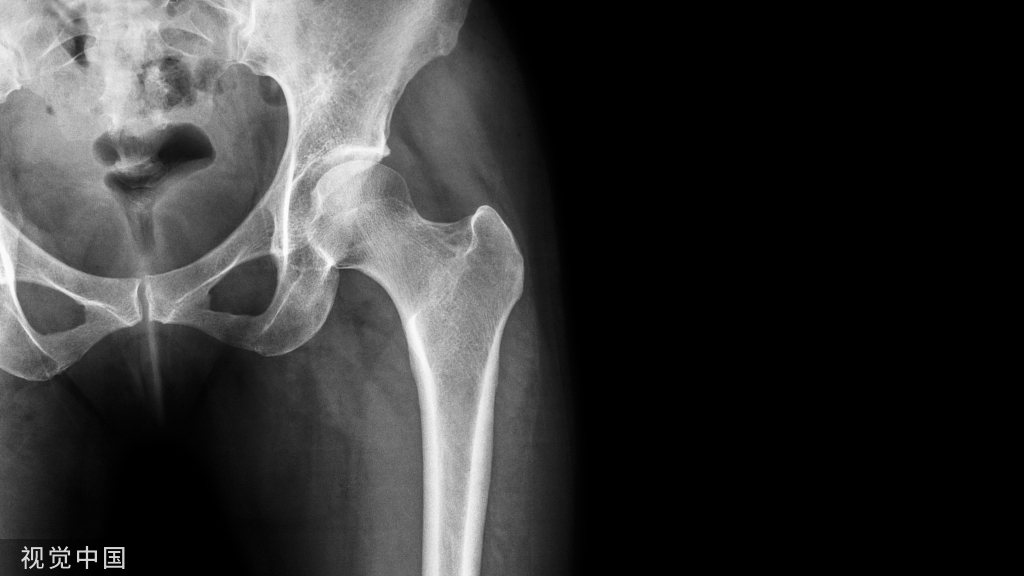

钙是人体所必需的物质,缺钙易致人体骨质疏松、浑身乏力和关节疼痛,严重缺钙者还易骨折和各种慢性病。